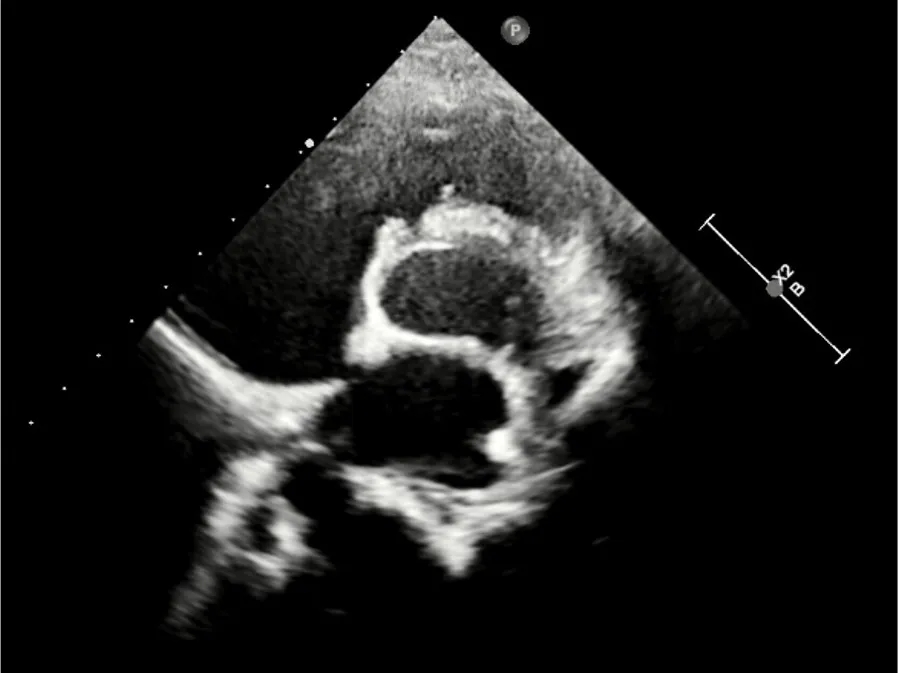

心脏彩超:心脏超声下可见两个封堵器双盘稳固夹持,无残余分流;

术后1个月心脏超声,房室水平皆无残余分流